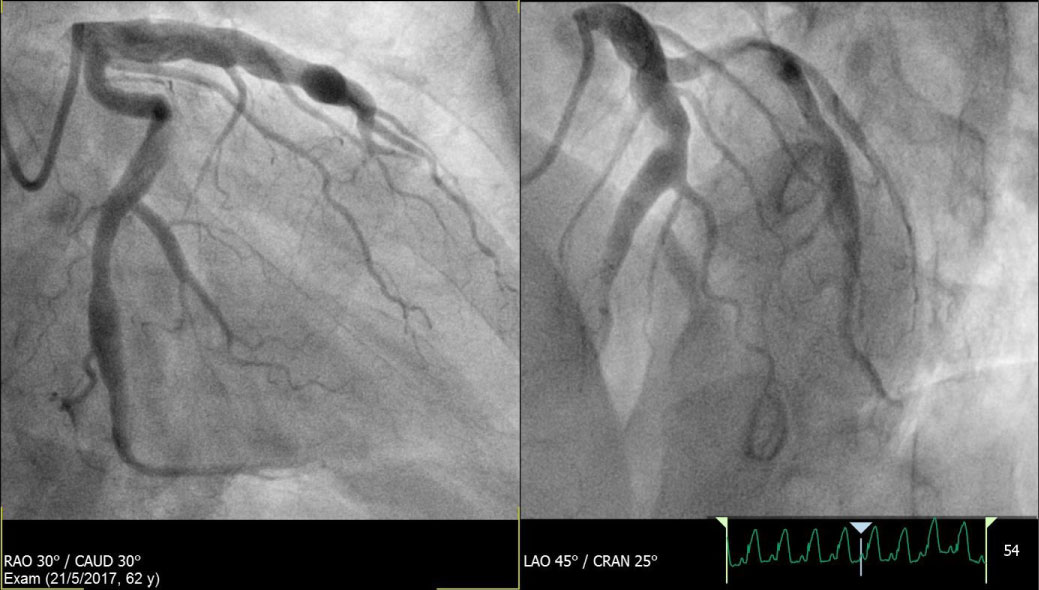

He was loaded with oral Aspirin 300 mg, Ticagrelor 180 mg and underwent an emergency percutaneous coronary intervention (PCI). A diagnostic coronary angiogram performed via the right radial artery approach showed huge aneurysmal coronary arteries with slow flow in the left coronary system as well as the right coronary artery (RCA) (See Figure 2a, Figure 2b, Figure 3a and Figure 3b). There was an acute thrombotic occlusion of the mid segment of a giant RCA aneurysm.

Figure 2: a,b) Showing aneurysmal changes in the left coronary arteries. View Figure 2

Figure 3: a,b) Showing acute thrombotic occlusion of the mid segment of the giant RCA aneurysm. View Figure 3